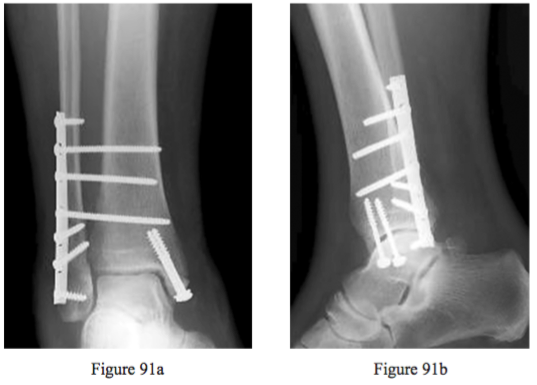

Question 91

Figures 91a and 91b are the current radiographs of a 60-year-old woman with type 1 diabetes mellitus who sustained a bimalleolar ankle fracture treated with open reduction and internal xation 6 weeks ago. What is the best next step?

PREFERRED RESPONSE: 4